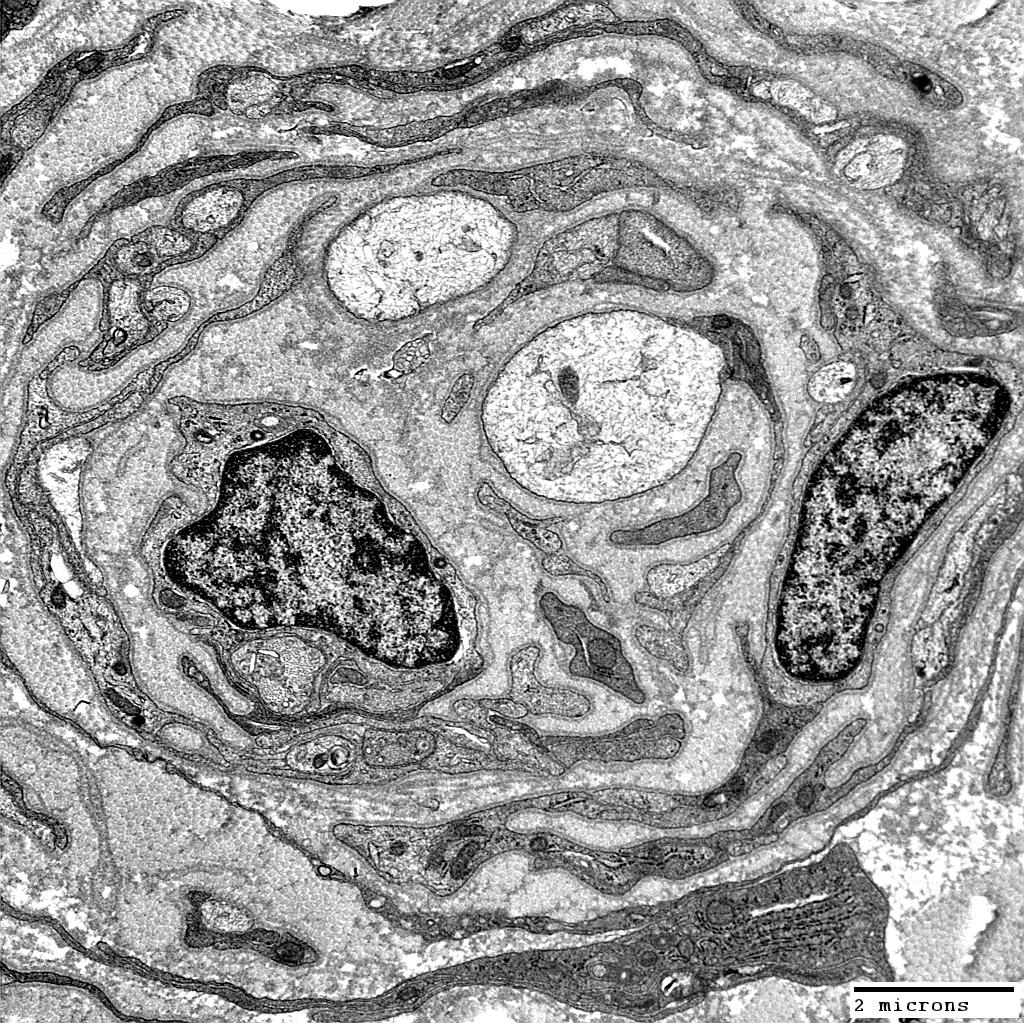

Onion bulbs, Large: Several layers surround thinly myelinated axons

Layers include

Schwann cell processes

Schwann cell basal lamina

Connective tissue

Outer rim: My be fibroblast process

Central axon: Thinly myelinated

Onion Bulbs: Around thinly myelinated axons

From: Robert Schmidt MD